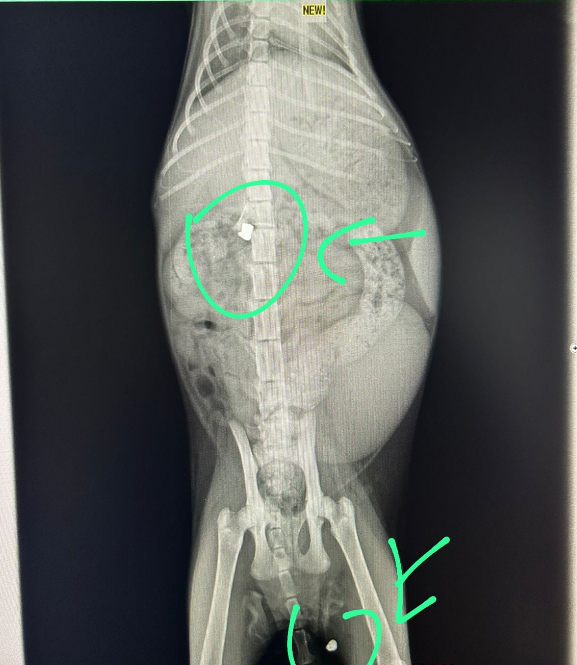

Vitória Raio-X Vitória

Vitória foi alvejada covardemente com dois tiros de chumbinho. Um projétil parou em sua medula, tirando-lhe os movimentos das patas traseiras. Durante meses, cuidamos dela com compressão na bexiga e remédios, mas ela partiu, deixando um vazio e o autor impune. Ela foi um símbolo de resistência e pureza.